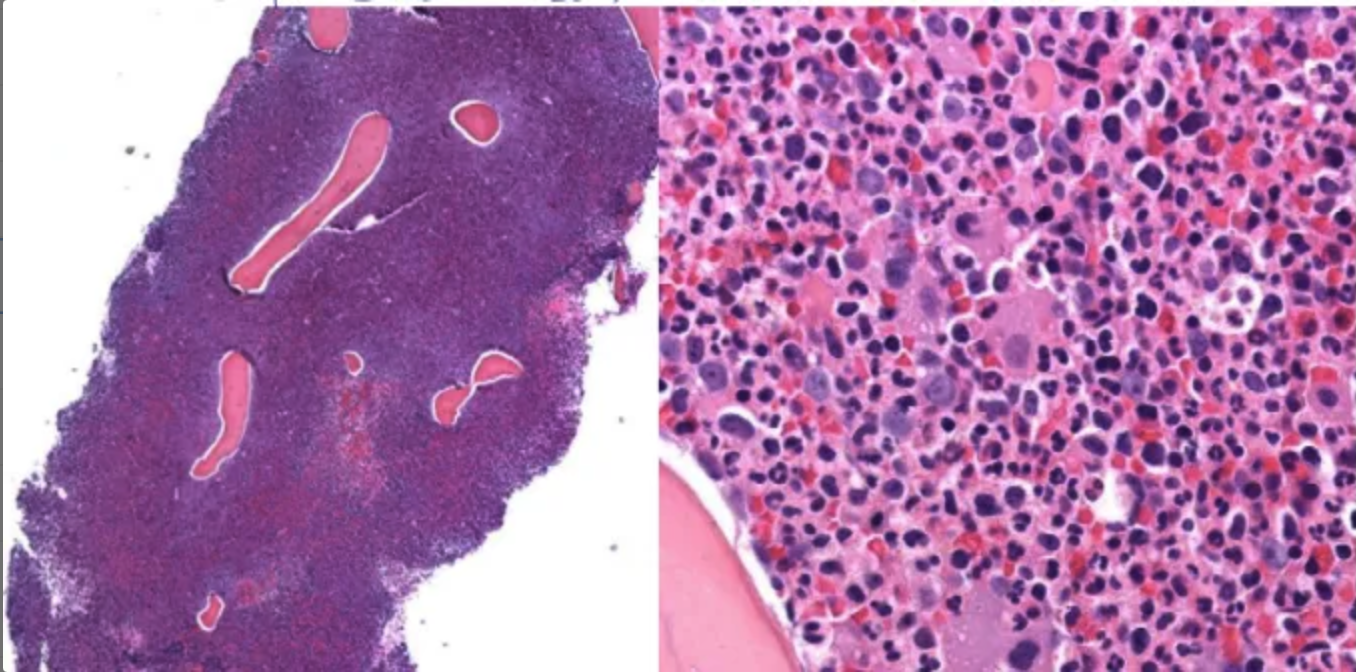

BM biopsy: complete replacement of hyper cellular marrow by blasts,

small round blue cell tumor면역화학염색

확진: 골수검사에서 myeloblast ≥ 20% or 특정한 genetic abnormality가 확인되는 경우